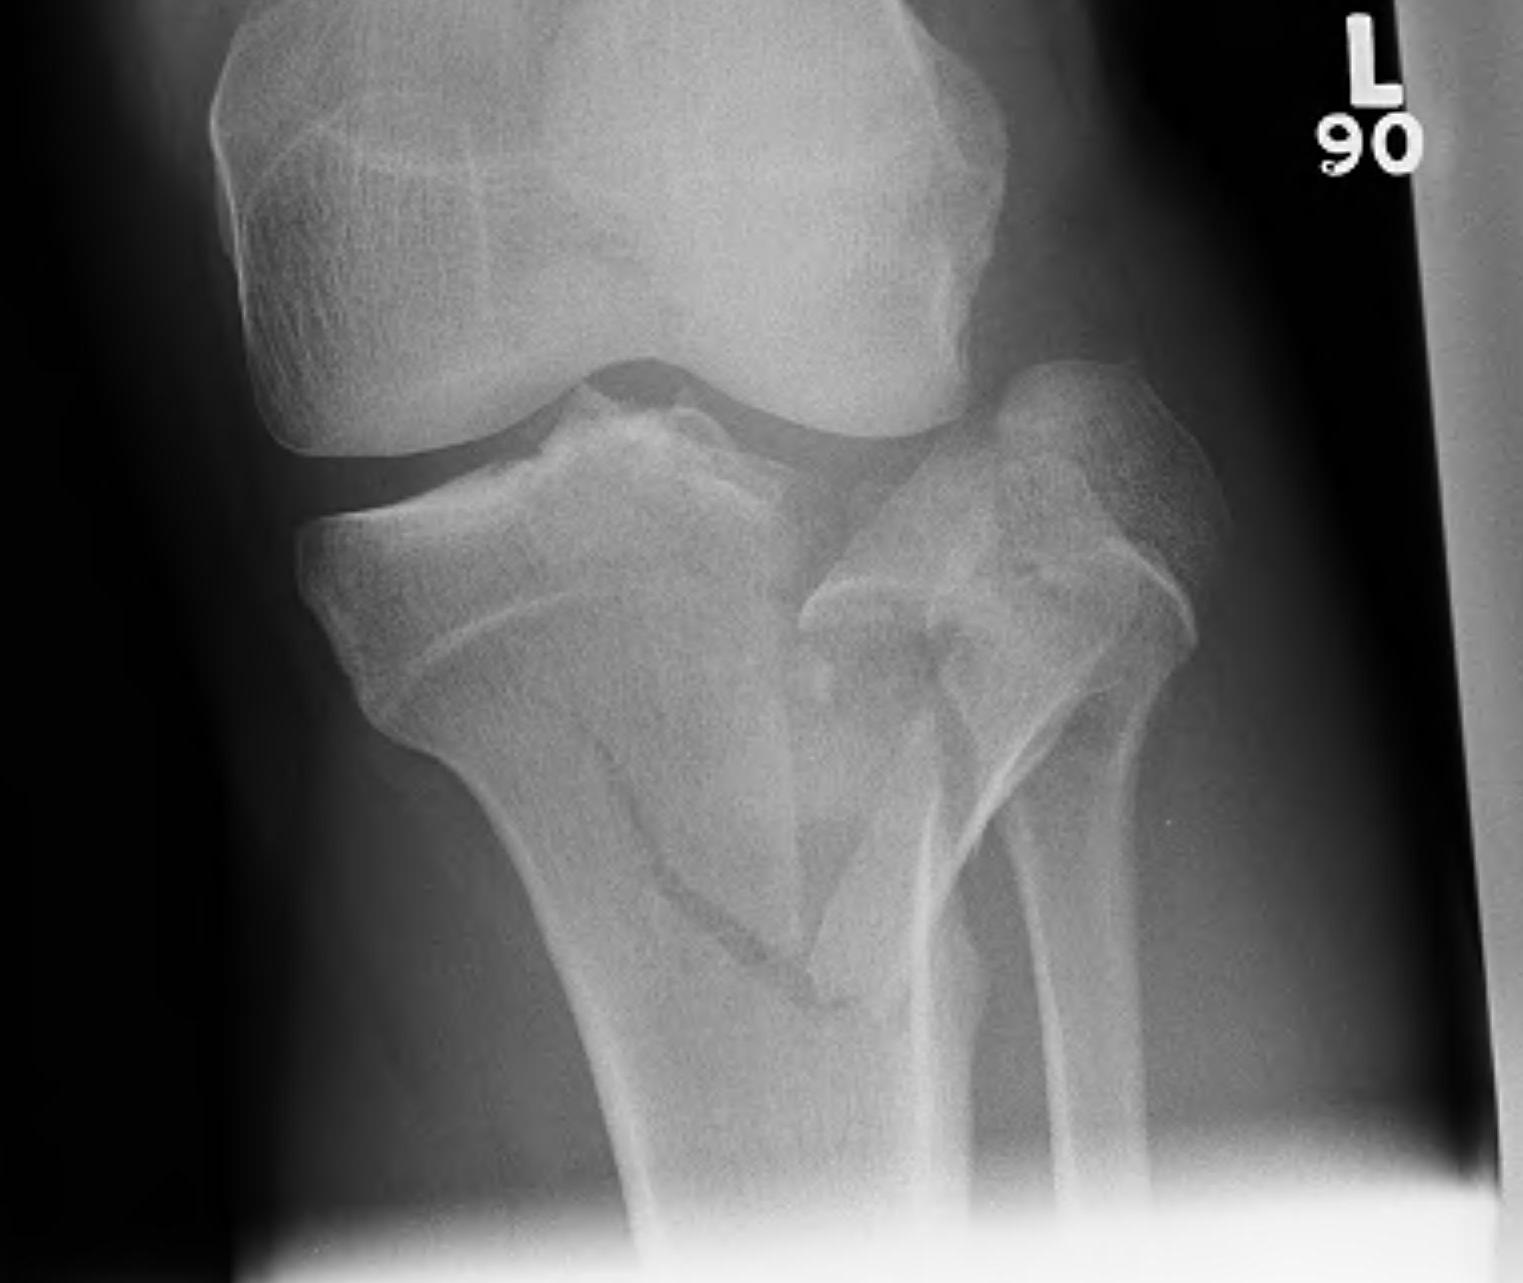

IV. Medial plateau & intercondylar eminence

- high velocity injury associated with ACL / LCL / CPN injury

- can be low injury / osteoporotic and often unreconstructable

- any fracture of medial plateau indicates high energy

- high incidence of soft tissue complications & poor outcomes